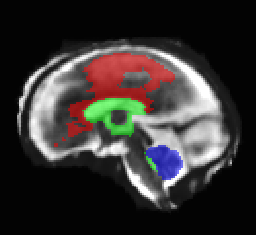

Limiting failures of machine learning systems is of paramount importance for safety-critical applications. In order to improve the robustness of machine learning systems, Distributionally Robust Optimization (DRO) has been proposed as a generalization of Empirical Risk Minimization (ERM). However, its use in deep learning has been severely restricted due to the relative inefficiency of the optimizers available for DRO in comparison to the wide-spread variants of Stochastic Gradient Descent (SGD) optimizers for ERM. We propose SGD with hardness weighted sampling, a principled and efficient optimization method for DRO in machine learning that is particularly suited in the context of deep learning. Similar to a hard example mining strategy in practice, the proposed algorithm is straightforward to implement and computationally as efficient as SGD-based optimizers used for deep learning, requiring minimal overhead computation. In contrast to typical ad hoc hard mining approaches, we prove the convergence of our DRO algorithm for over-parameterized deep learning networks with ReLU activation and a finite number of layers and parameters. Our experiments on fetal brain 3D MRI segmentation and brain tumor segmentation in MRI demonstrate the feasibility and the usefulness of our approach. Using our hardness weighted sampling for training a state-of-the-art deep learning pipeline leads to improved robustness to anatomical variabilities in automatic fetal brain 3D MRI segmentation using deep learning and to improved robustness to the image protocol variations in brain tumor segmentation. Our code is available at https://github.com/LucasFidon/HardnessWeightedSampler.